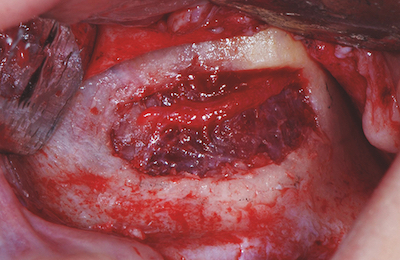

Ensuite, Christine Bach (entretien à lire ici), chirurgien ORL à l’hôpital Foch, nous alertera sur les pathologies sinusiennes importantes. Mais aussi, elle débattra, avec la complicité de Jean-Yves Cochet, endodontiste, sur les moyens diagnostiques permettant de différencier l’étiologie sinusienne de l’étiologie endodontique. Et cela, bien sûr, à travers différentes situations cliniques.

Jean-Yves Cochet (entretien à lire ici) prendra les manettes en début d’après-midi pour dresser un état clinique des pathologies sinusiennes d’origine endodontique. Il nous fera part de son expertise en tant qu’endodontiste régulièrement confronté à des cas complexes. Il délivrera les clés thérapeutiques pour optimiser la guérison grâce aux traitements endodontiques mais, nous alertera, aussi, sur les cas où ces traitements sont exposés à un risque d’échec.

- La communication bucco-sinusienne : conduite à tenir